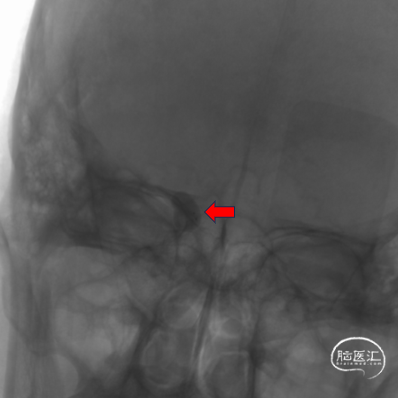

栓塞金球囊半充盈堵塞瘘口,ICA海绵窦段以远显影。

栓塞金球囊全充盈堵塞瘘口,ICA海绵窦段以远显影良好,但瘘口有少量侧漏。

10min后显示瘘口侧漏消失。